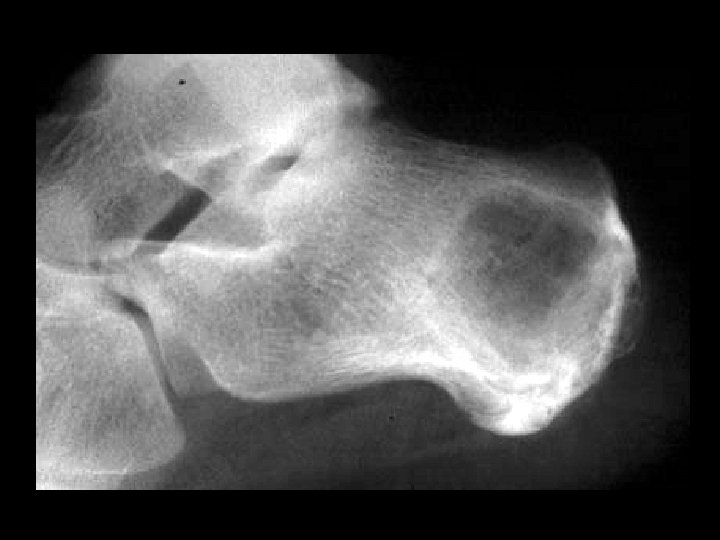

Calcaneal Ewing’s sarcoma • Findings: – Permeative lesion in the calcaneous – Cortical disruption and slight periosteal reaction • ddx: – Lymphoma – Metastasis/myeloma – Infection – Langerhan’s cell histiocytosis